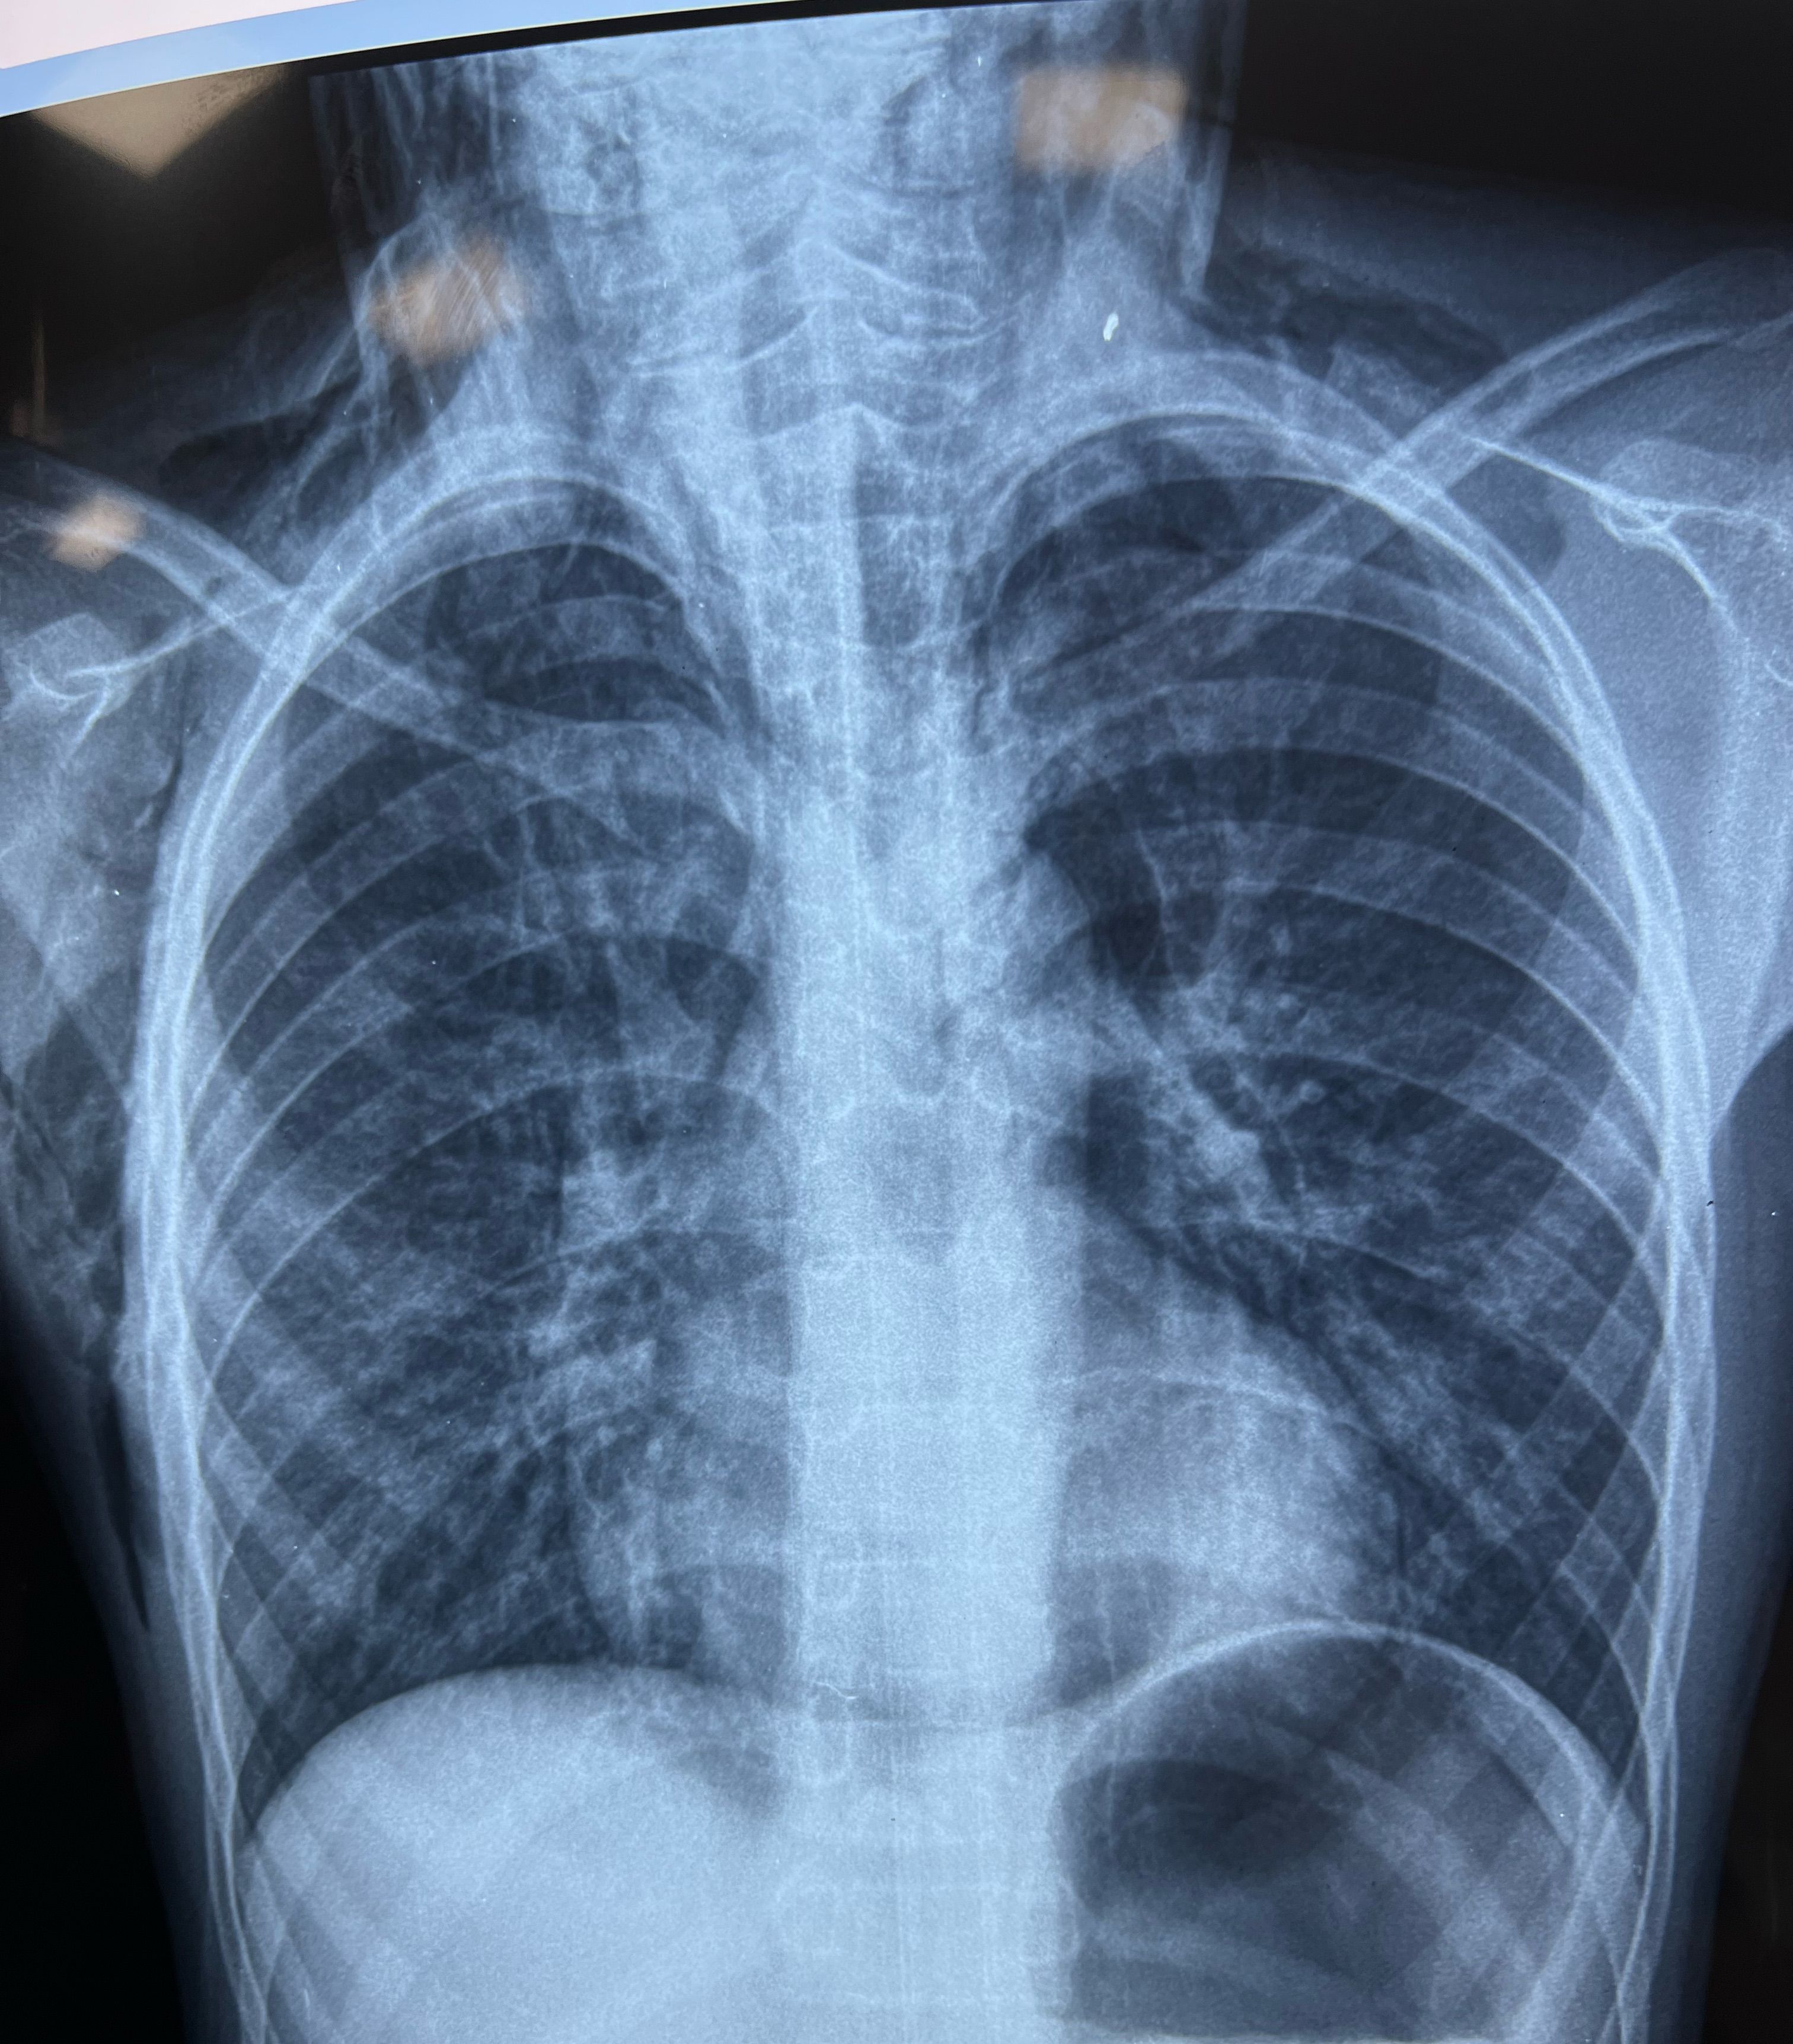

14 year’s old male RTA present after 1hr with neck swelling and SOB chest clear abdomen soft GCS 15/15 Spo2 90%-o2 HR:102 beat/min Dx